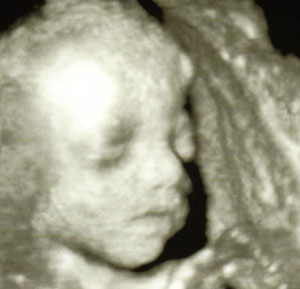

Rakok már fel képet a drágámról.